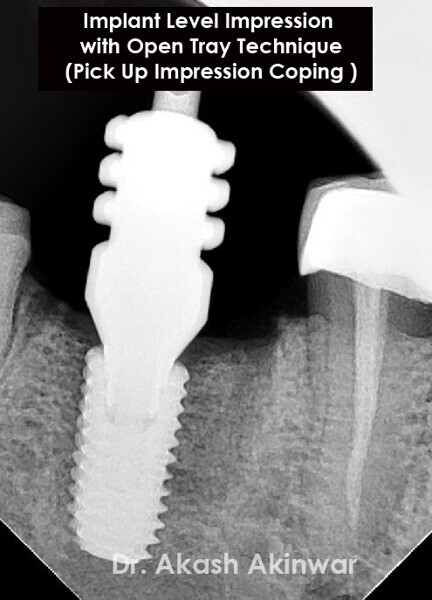

Flapless Single Implant Placement with Screw Retained PFM Prosthesis: Dr Akash Akinwar